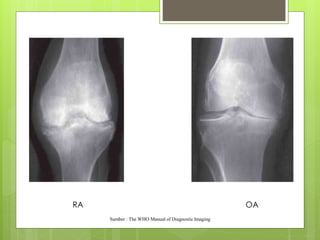

Perbedaan Gambaran Deformitas yang terjadi pada RA dan OA

RA OA

Sumber : The WHO Manual of Diagnostic Imaging

Perbedaan Gambaran Deformitasyang terjadi pada RA dan OA

RA OA Sumber :The WHO Manual of Diagnostic Imaging